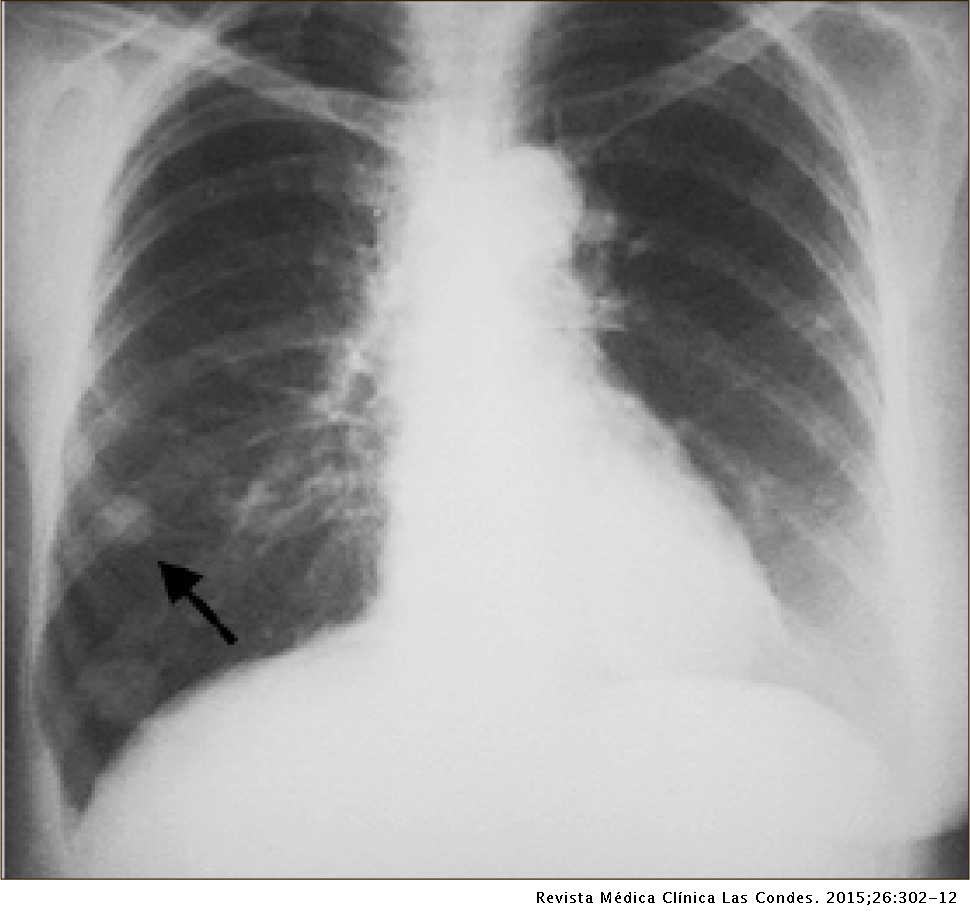

Tipo de patrón frecuente en enfermedades granulomatosas:

Nodular

Un nódulo solitario es frecuente por enfermedad:

Granulomatosa por tuberculosis

Muchos nódulos indican:

Metástasis